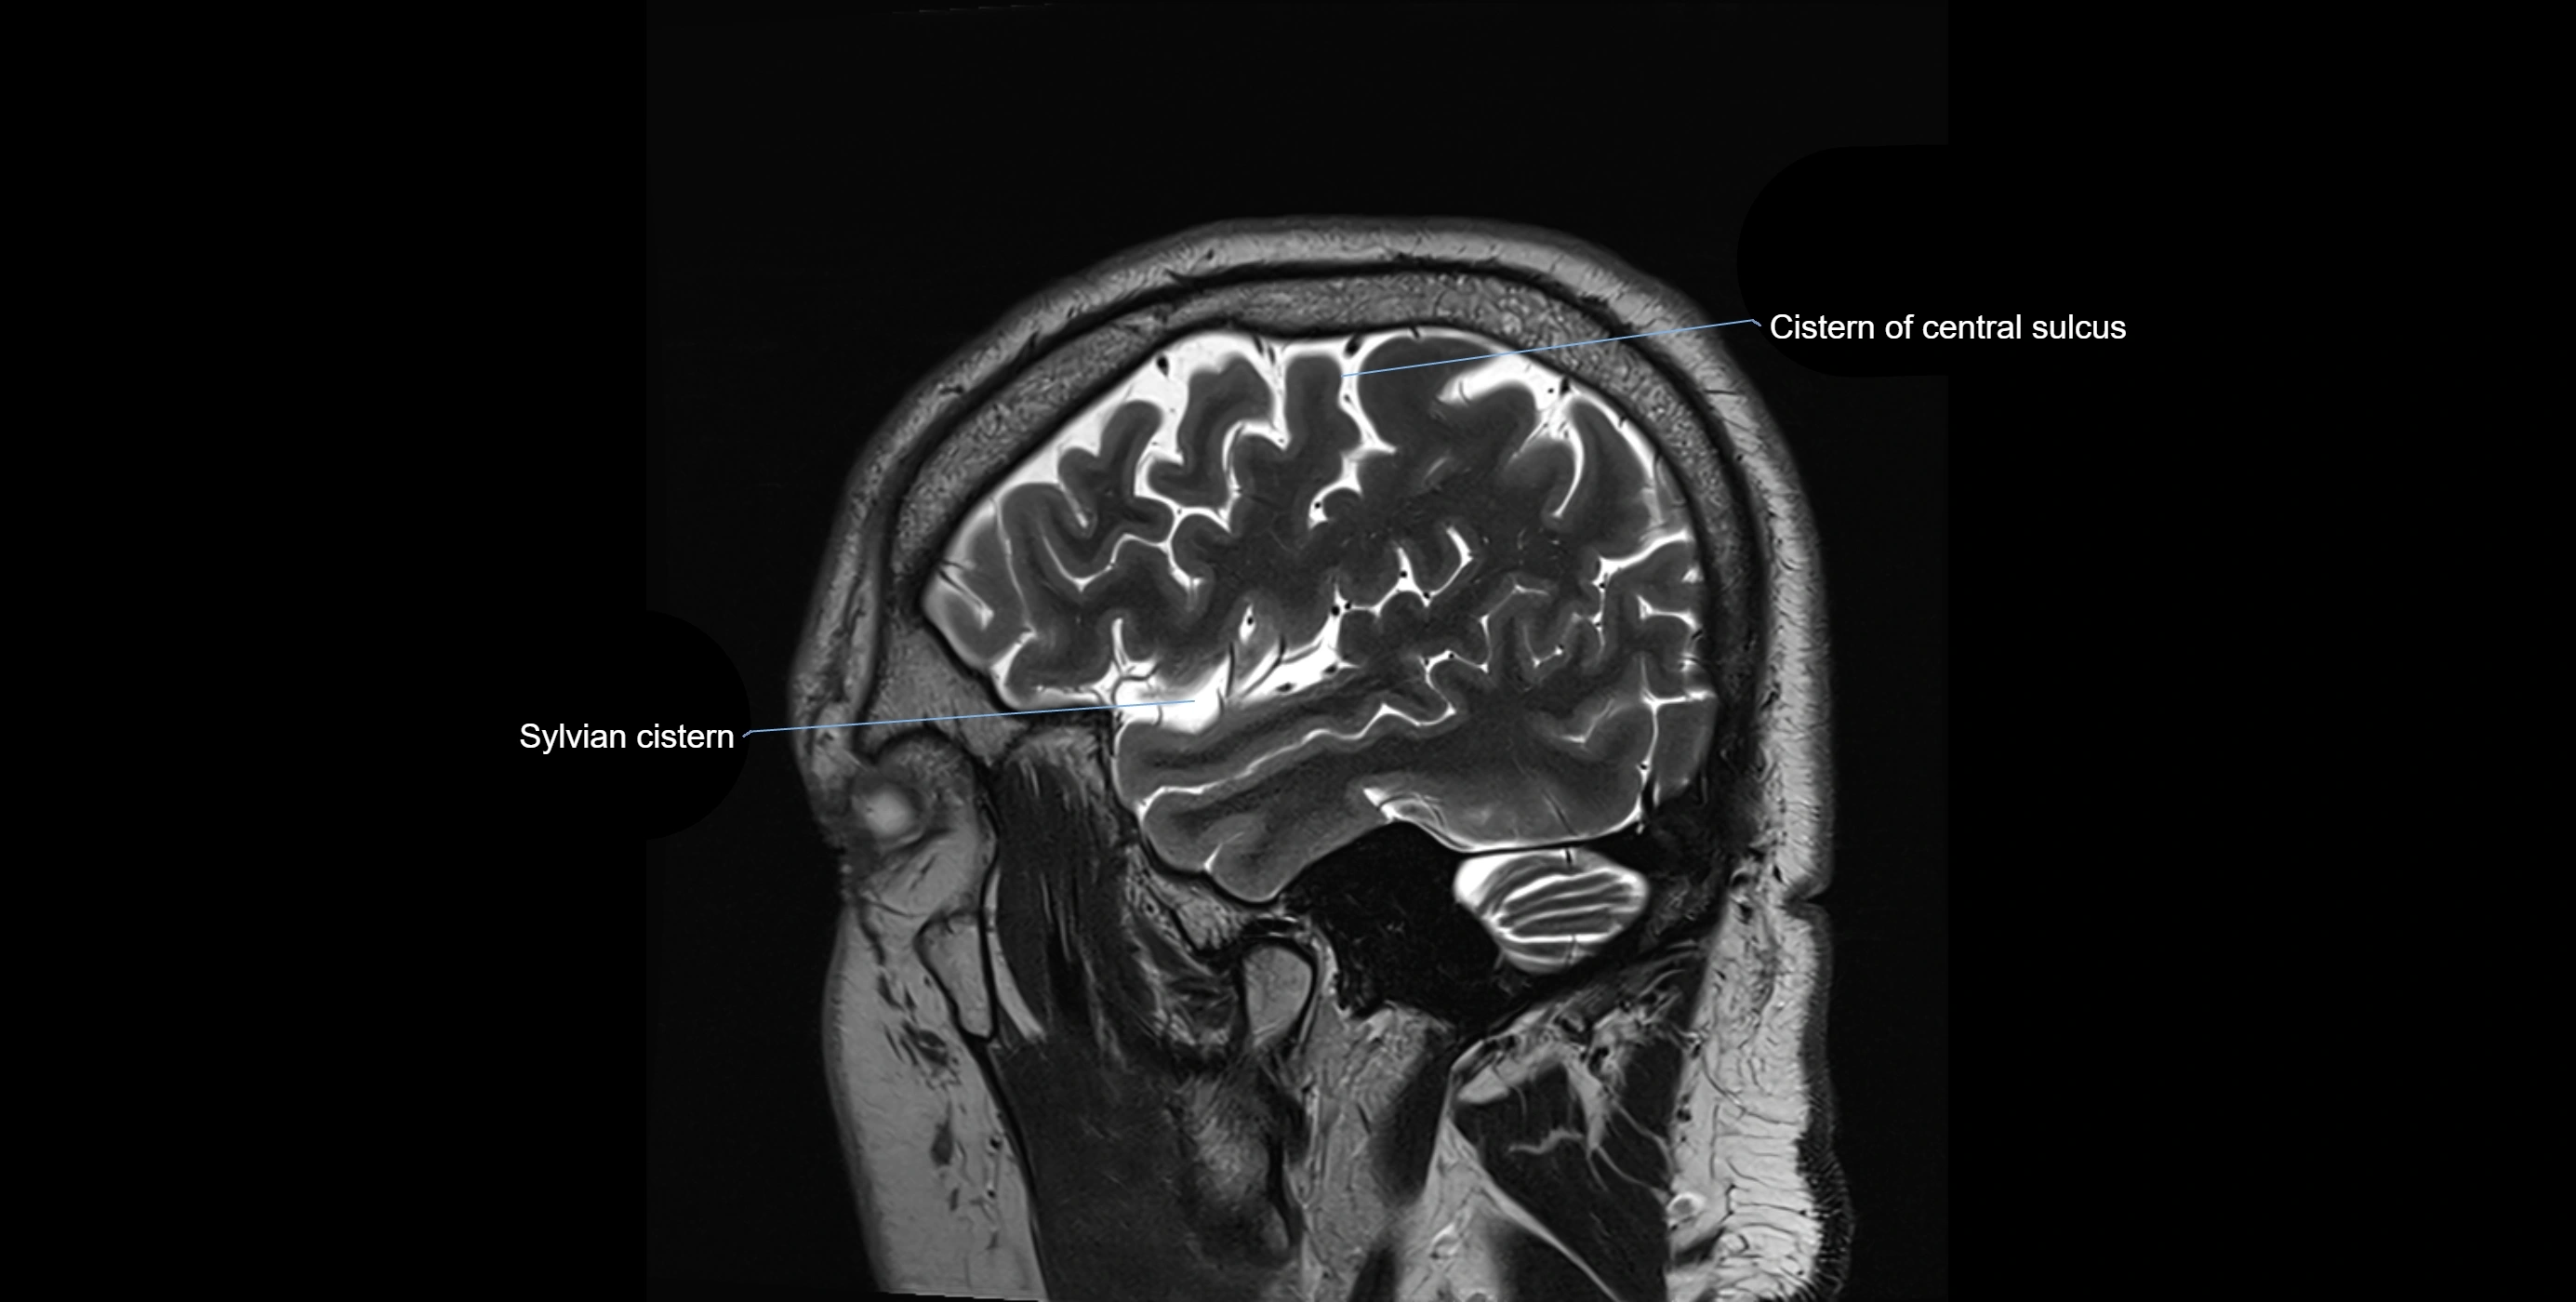

Ambient cistern

The ambient cistern is a paired, narrow, and elongated subarachnoid space located bilaterally along the lateral aspect of the midbrain. It serves as a conduit between the interpeduncular cistern anteriorly and the quadrigeminal cistern posteriorly. This cistern houses critical neurovascular structures, including parts of the posterior cerebral artery, superior cerebellar artery, trochlear nerve (cranial nerve IV), and the basal vein of Rosenthal. It plays an important role in the circulation of cerebrospinal fluid (CSF) and provides an anatomical corridor for various vessels and nerves passing around the midbrain.